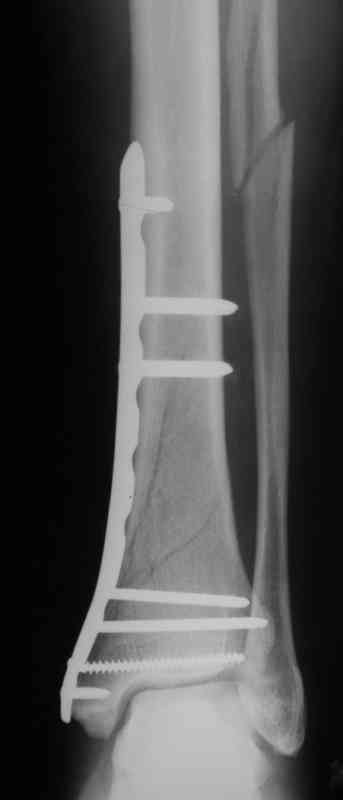

Выполнил MIPO предизогнутой метафизарной LCP

И все же немного критики:1) Вы добивались анатомичной репозиции, которая требует абсолютной стабильности, которая в свою очередь возможноа только в условиях межфрагментарной компрессии. Пластина уложена как мостовидная, не хватает стягивающнго винта. 2) есть укорочение малоберцовой кости, необхордимо восстановить ее длину! В таком виде я бы не стал разрешать раннюю нагрузку. Добавить самую малость: стягивающий винт и остеосинтез малоберцовой кости и больной может наступать сразу.

В этом случае остеосинтез выполнялся малоинвазивно и я не добивался абсолютной стабильности преднамеренно. Стабильность относительная и ст. её зависит от механических свойств импланта;возможно, нужно было взять длиннее пластину, увеличив её рабочую длину

Все справедливо для оскольчатого перелома, когда вы не добиваетесь анатомичной репозиции. При простом переломе адекватной будет анатомичная репозиция, и она у Вас получилась закрыто. Если Вы изначально предполагали относительную стабильность, то штифт позволил бы более раннюю и агрессивную реабилитацию

В последствии стал выполнять мостовидную фиксацию не только при оскольчатых переломах, но и при простых, прооперировал около 30 голеней, сращение наступило у всех периостальной мозолью.